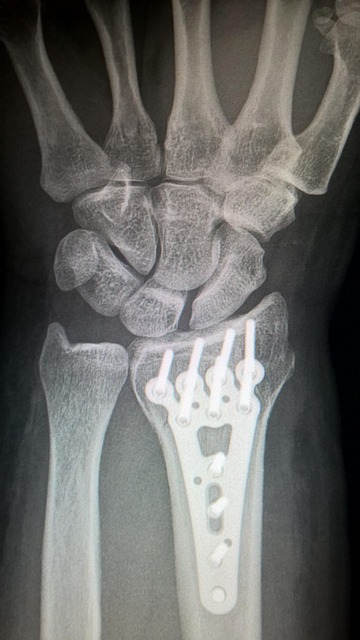

- Recovering from injury or surgery